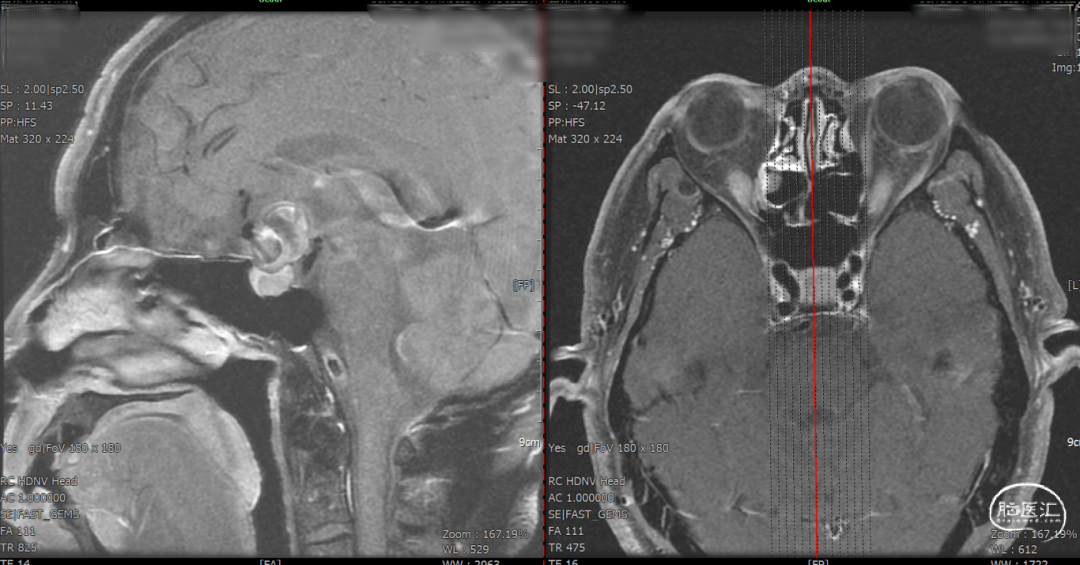

术后一天检查。

1.该病例通过多方面考虑,选择密网支架植入术手术方案,且锚定区仅为右侧ACA,不影响对侧血流。

2.Surpass Evolve输送顺滑,跟踪性强,在输送支架过程中,XT-27微导管头端稳定。

3.Surpass Evolve打开顺利,打开即贴壁。尤其支架的远端打开顺利,减少了小血管中释放密网支架的操作,降低了术中并发症的风险。